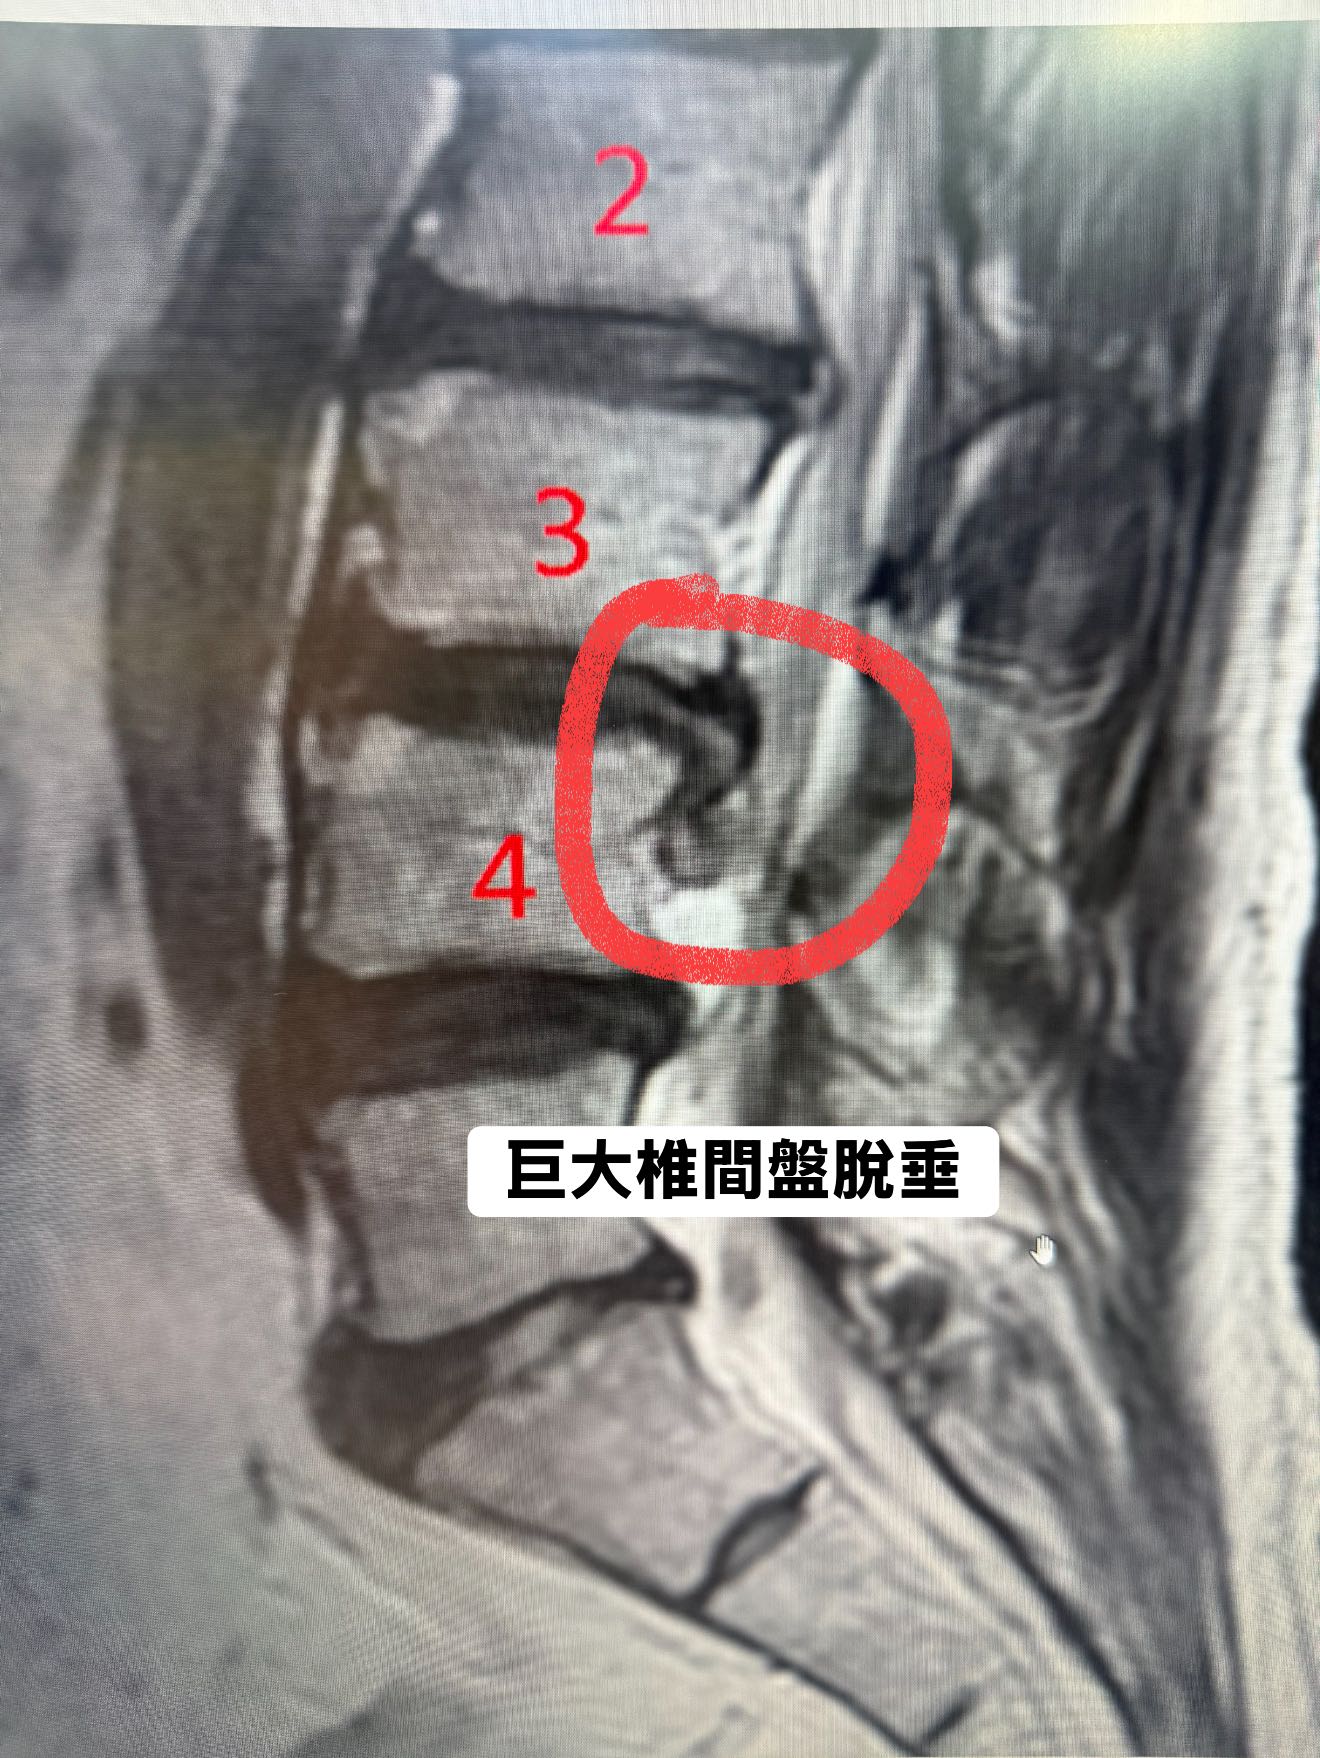

主角是一位理性而內斂的工程師,工作上精準冷靜,生活中邏輯至上。今年二月,他前往日本滑雪,卻在一次重摔中造成腰椎劇烈傷害。返國後的 MRI 顯示:L3/L4椎間盤破裂並脫出,壓迫神經根。臨床症狀典型且嚴重:坐骨神經痛、單側下肢麻木、反射異常、夜間抽痛,排尿頻率改變。

我看著他的 MRI,也看著他走進來時不自然的步態與臉上壓抑的焦慮。影像顯示突出髓核壓迫神經管道甚鉅,接近手術標準。但我知道,一旦動刀,風險與後果非輕。

最後應該會有人問我說那治療之後的椎間盤突出是否有吸收呢?答案是有,但是同一張前面的核磁共振,不管是縱切片以及橫切面都有大幅度的吸收,不過那個也不是我討論的範圍了,因為就算不做任何治療躺平半年也會自己吸收,但我相信沒有任何患者可以躺平半年